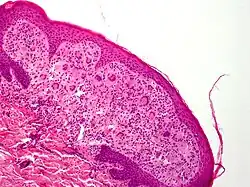

Tumeur cutanée

Une tumeur cutanée se développe à partir d'un ou plusieurs des composants de la peau. En dermatologie, on appelle tumeur un certain nombre de lésions dont la plupart de celles citées ci-dessous ne sont pas des lésions malignes mais des proliférations cellulaires regroupées en une masse palpable.

Les tumeurs de la peau présentent des caractéristiques propres permettant de différencier leur origine ou leur type. Leur consistance, leur nombre, leur couleur, leur adhésion aux plans profonds du tégument. On étudie également l'ensemble du tégument et on pratique un examen clinique complet lors du bilan étiologique.